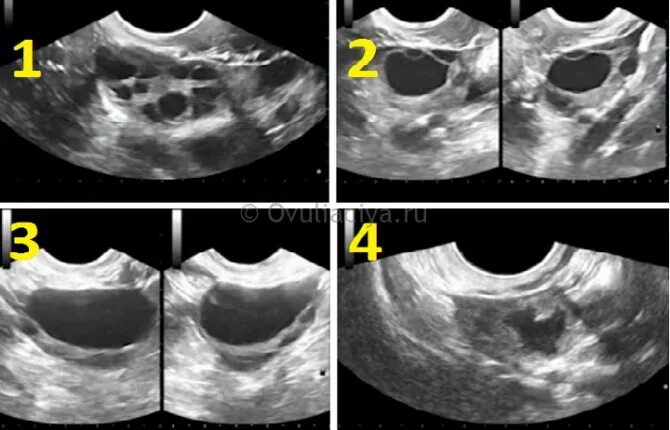

Максимальный размер фолликула